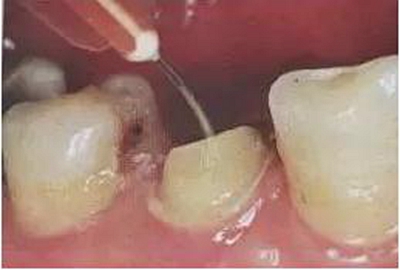

5、根管酒精消毒

這一步驟一定不能省,纖維樁完全是依靠粘接固位的,根管內(nèi)壁任何雜物都會(huì)影響粘接效果,就算EDTA、NACLO等髓腔消毒藥物對(duì)粘接都有很大的影響,如果治療后要做纖維樁,在根充時(shí)就應(yīng)該注意不要使用含有丁香油的糊劑。

6、用蒸餾水沖洗根管

用蒸餾水將根管內(nèi)雜物和酒精全部沖洗出來(lái)。

7、根管干燥

用紙尖反復(fù)將根管內(nèi)的水分全部吸干,告訴大家一個(gè)技巧,可以將紙尖前端細(xì)的部分減掉,這樣吸水效果會(huì)更好。